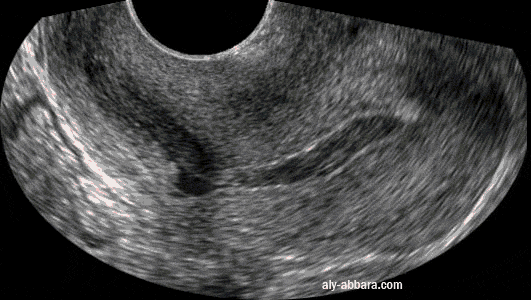

La présence d'une petite lame du sang dans la cavité utérine (après un avortement complet, sans curetage, à 6 SA) permet de bien identifier l'endomètre qui est très fin, et aussi curieusement, on peut facilement constater la présence d'un diverticule ou une sorte de cul-de-sac dans la paroi postérieure de l'utérus, dans la région isthmique. |